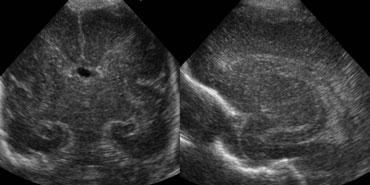

Xuất huyết nội sọ độ 2

Hình bên trái là xuất huyết nội sọ độ 2.

Trên mặt cắt đứng ngang, chỉ nhìn thấy khoang vách trong suốt.

Cả hai não thất bên đều chứa đầy máu, nhưng không có giãn não thất.

Hình bên trái là cùng bệnh nhân sau 3 ngày.

Các não thất giãn rộng và có hình ảnh hình thành cục máu đông.

Não úng thủy thứ phát xảy ra vài ngày sau xuất huyết độ 2 không nên bị nhầm lẫn với xuất huyết độ 3.